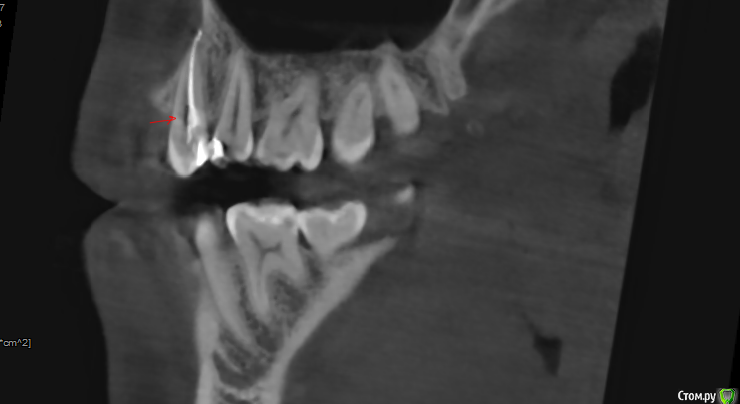

Прикрепляю скриншоты КТ. Подскажите, пожалуйста, что это может быть под красной стрелкой на снимках 2 и 3?

post-58215-0-59155600-1573918890_thumb.png

Рентген - это дополнительный метод исследования и диагностики. Поэтому только на основании снимка и субъективных ощущений пациента невозможно поставить диагноз и дать полный правильный ответ. Мне было бы важно также посмотреть состояние соседних зубов, особенно зуба 1.5 (перкуссия, подвижность, состояние тканей пародонта, витальность, патологическая стираемость, температурные пробы...). Делать упор только на леченный 1.4 зуб неправильно. Хотя допускаю, что и он может быть причиной всех болезненных ощущений (например трещина в корне, вывод материала, перфорация боковой стенки, близость гайморовой пазухи, лор статус, неврологический статус.... Да чего только не может быть).